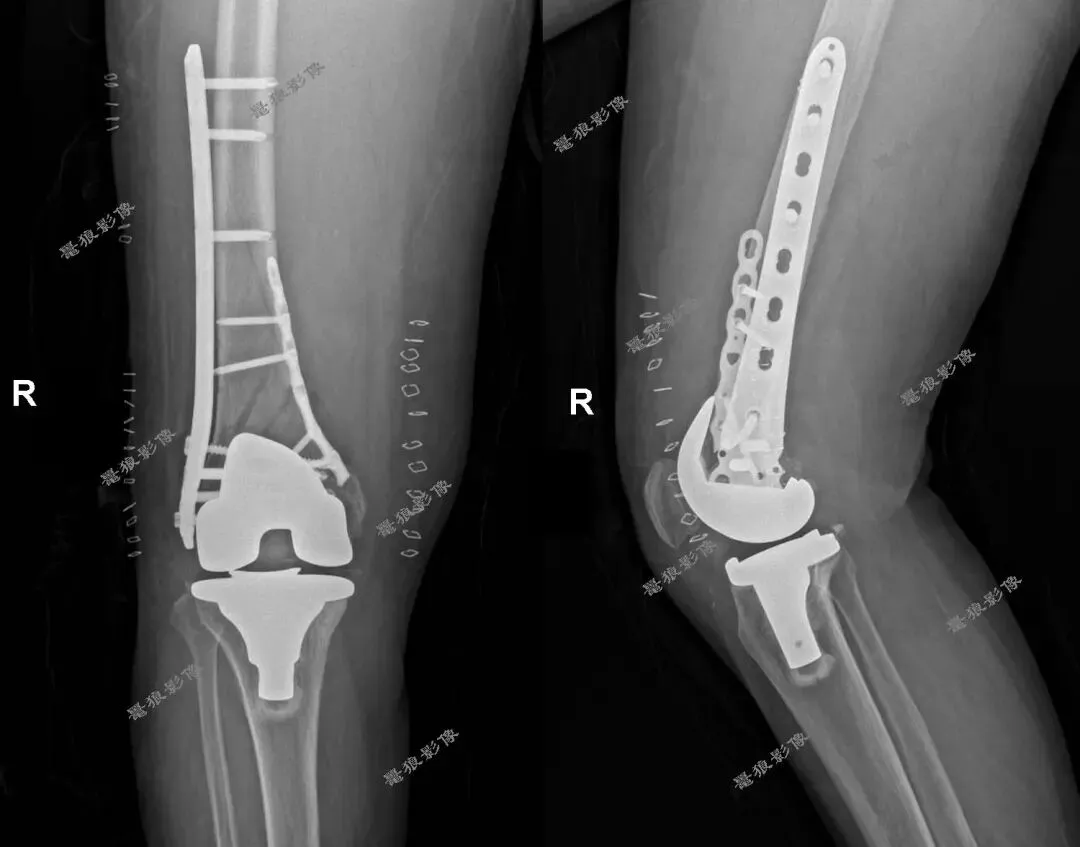

外伤后:

右膝关节置换术后股骨假体周围骨折。

右股骨假体周围骨折切开复位内固定术后。